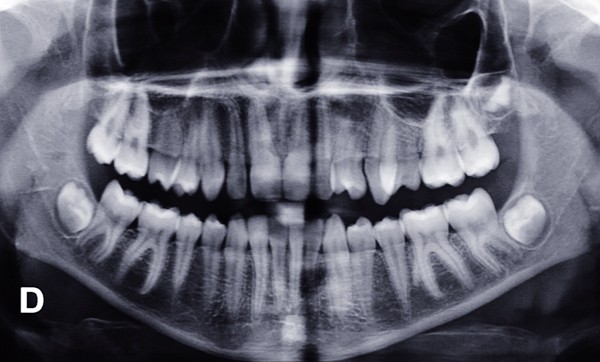

Sur le plan occlusal et dentaire, on observe une classe III molaire et canine à gauche, une proalvéolie maxillaire, une occlusion inversée au niveau des 15/46 et 25/35-36, une non concordance des milieux incisifs et une transposition complète de 23 et 24 (fig. 2 et 3).